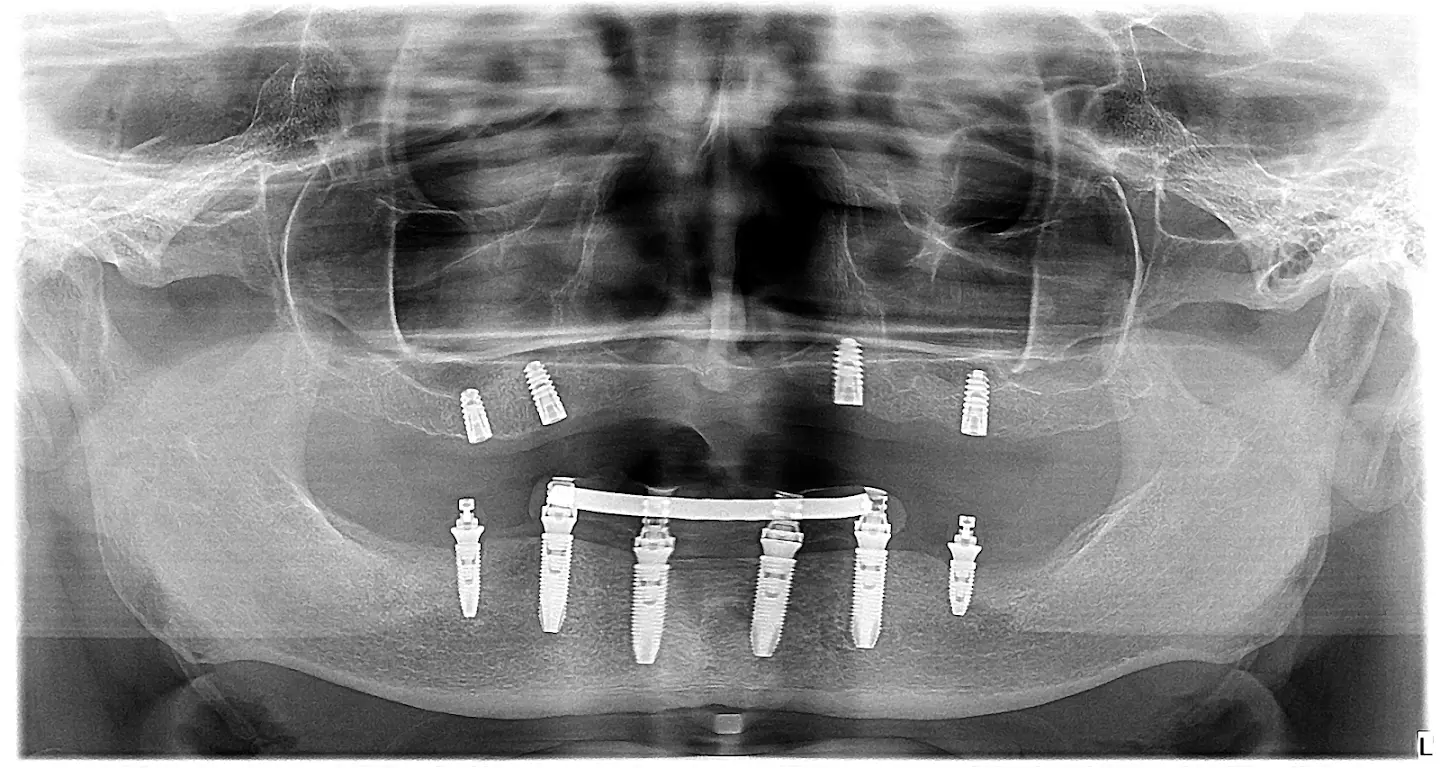

ksenia - opt shot - all on 6 all on 4 dental implants

Reconstruction of both jaws with the ALL ON 4 method

Ksenija came to us with full confidence on her brother's recommendation. Ksenia sent her 3D recording via email, so she didn't come to the first live screening. We placed 4 in the lower jaw dental implant and Xenia received temporary teeth in 24 hours using the all on 4 method, while we had two potential options in the upper jaw - if we were to do fixed work, we would have to place zygomatic implants, or to make Ksenia a clasp prosthesis and let's place 4 standard dental implants. Ksenia opted for the second option, so we set 4 for her Ankylos dental implant and a clip-on prosthesis, while below were a hybrid bridge.

We removed existing unhealthy teeth

We installed 8 dental implants - 4 in the upper jaw (Ankylos) and 4 (Nobel biocare) in the lower jaw

We placed a clip-on prosthesis in the upper jaw

We placed a fixed hybrid bridge in the lower jaw